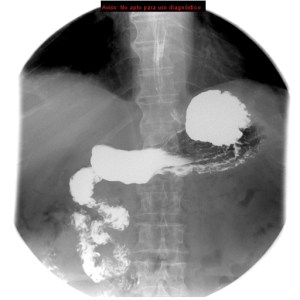

Se solicita tránsito intestinal baritado por proceso actual de vómitos, estreñimiento, historia de sangrado digestivo bajo y anemia sin hallazgos de malignidad tras la realización de colonoscopia y TAC.

Inestino delgado localizado en toda su integridad en hemiabdomen derecho. El ángulo de Treitz (unión entre duodeno y yeyuno) que es la estructura más fija del sistema digestivo, no se encuentra en su localización habitual, lo cual es un hallazgo diagnóstico muy importante.

Se revisarón estudio previos, en un enema baritado y TC se observó:

Enema baritado con ciego (con apéndice visible) en posición anómala, localizado en hipocondrio izquierdo. TAC de adomen con signo de remolino o Twister de vasos. Otro hallazgo sería encontrar la VMS a la izquierda de la AMS.

Diagnóstico: MALROTACIÓN INTESTINAL.